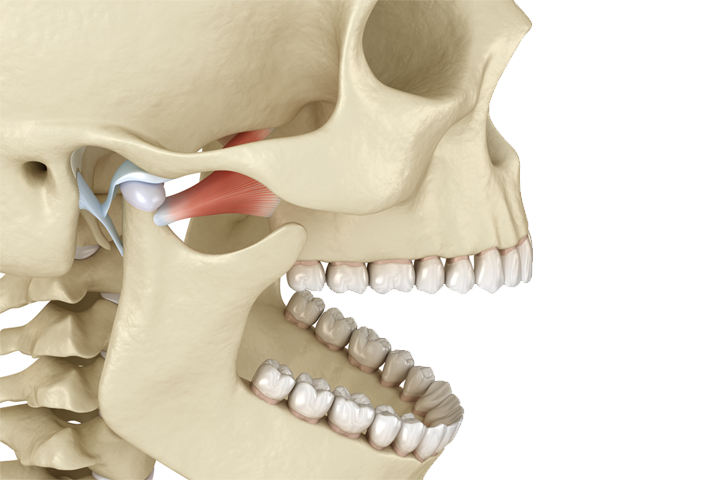

Articulación Temporomandibular

La articulación temporomandibular (una a cada lado de la cabeza), es la articulación formada por la parte superior de la mandíbula y el hueso temporal del cráneo . Este hueso actúa como una bisagra deslizante y, en ocasiones, puede presentar problemas debido a la complejidad de los movimientos que realiza. Estas articulaciones son las que permiten que la mandíbula se mueva hacia delante y hacia atrás, por lo que son indispensables para realizar funciones básicas como masticar o hablar.

Los problemas que puede causar este síndrome son:

• Dificultad para abrir y cerrar la boca

• Dificultad para morder y masticar

• Chasquido al abrir y cerrar la boca

• Dolor facial, de oído y/o de cabeza

• Dolor o sensibilidad en la mandíbula

El síndrome puede tener distintas causas, una causa muy común es el estrés físico sobre las estructuras cercanas a la articulación, como son los músculos de la mandíbula, la cara y el cuello, los dientes, los ligamentos, los vasos sanguíneos o los nervios cercanos. Otras causas pueden ser el rechinamiento de los dientes (bruxismo), una mala mordida, una mala postura, una dieta deficiente, la falta de sueño o la artritis.